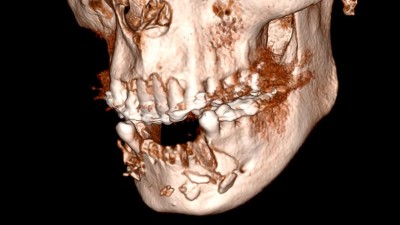

Rekonstruktion des Unterkiefers nach Trauma mithilfe von resorbierbarer Magnesiummembran und allogenem Knochen (Link öffnet in neuem Fenster)

Das vorliegende Fallbeispiel zeigt, dass die Verwendung einer resorbierbaren Magnesiummembran in Kombination mit allogenem Knochenmaterial eine effektive Methode zur Rekonstruktion eines atrophierten Kieferknochens in der Unterkieferfront nach Trauma darstellt. Die hier verwendeten Keramikimplantate sind eine Alternative zu herkömmlichen Titanimplantaten, wobei die Erfahrungen hinsichtlich des Langzeitüberlebens der Keramikimplantate noch begrenzt sind.

Sofortversorgung mit verschweißtem Metallgerüst - Abbildung 13/© Johannes Petschelt, Sofortimplantation mit Sofortbelastung - Abbildung 1/© Rudolf Kraus, Digitales Ergebnisbild eines präoperativen Scans Unterkiefer: Zahnloser Kieferkamm. Von links nach rechts sind die Positionen 46, 44, 33, 36 markiert/© F. Stelzle | ZI Zahnärztliche Implantologie (2)·2:92-96, Inseriertes Implantat regio 36 nach Entfernung der Osteosyntheseschrauben. Im Kieferkamm ist ein Knochenblocktransplantat sichtbar/© M. Masthoff | ZI Zahnärztliche Implantologie (2)·2:80-84, Bild einer dreidimensionalen digitaler Volumentomographie: Kiefer und Zähne sind zu sehen. Im Unterkiefer fehlen Zähne 33-44./© Universitätsmedizin Mainz, Bild intraoral eines Oberkiefers mit Scanbodies/© Inga Boehncke | ZI Zahnärztliche Implantologie (2)·1:34-40, Ausgangssituation: Zahn 41 mit Komposit-Eckenaufbau/© D. Butzmann | ZI Zahnärztliche Implantologie (1)·4:224-227, Einzelröntgenaufnahme: regio 36 und 37 wurden 2 Straumann-Implantate RN 4,1 mit der Länge 10 mm gesetzt/© Frank Sahm | ZI Zahnärztliche Implantologie (1)·4:212-213, Eingesetztes Individuelles Healing Abutment und Weichgewebsstabilisierung. Das Abutment dichtet die Alveole vollständig ab./© N. Erhard, T. Erhard-Sosna, R. Sader, J. Lorenz | ZI Zahnärztliche Implantologie (1)·4:214-223, Während die Quadrantenstütze des Vertikalextraktorsystems auf den Zähnen 12, 13, 22 und 23 aufliegt, wird Zahn 21 mit einer Seilwinde nach dem Flaschenzugprinzip herausgezogen/© S. Kistler | ZI Zahnärztliche Implantologie (1)·4:228-237, Klinischer Befund: prothetische Versorgung Regio 14, 13, 23, 24 und 34, 33, 43, 44, 28 Jahre post operation/© A. Koch, A. Nitsch, F. Danneil | ZI Zahnärztliche Implantologie (1)·2:90-92, Postoperative 3D-Rekonstruktion der Digitalen Volumentomographie. Zu erkennen sind das patientenspezifische Implantat (PSI) und seine Verankerung am Jochbeinkörper sowie der paranasalen und anterioren Maxilla/© F.S. Siegberg, P. W. Kämmerer, B. Al-Nawas, D. G. E. Thiem | ZI Zahnärztliche Implantologie (1)·2:84-88, Oberkiefer: Hart und Weichgewebsdefizit. Zusätzlicher tiefer knöcherner Defekt von 5 mm mesial des Zahns 22/© A. Rudolph | ZI Zahnärztliche Implantologie (1)·2:108-111, Zahnersatz in situ vor abschließender Unterfütterung mit Randerweiterung/© J. Behring | ZI Zahnärztliche Implantologie (1)·2:100-106, Frakturierter Zahn 34 in situ/© J. Behring | ZI Zahnärztliche Implantologie (1)·1:40-43, Front in Okklusion/© S. Egger, M. Greven, Ch. Berg | ZI Zahnärztliche Implantologie (1)·1:20-27, Fallbericht - Verspäteter Lückenschluss - Abb1/© R. Kraus | ZI-Zahnärztliche Implantologie (1) : S.38-42, Wahl des Analgetikums in der Zahnmedizin/© Heimes D, Kämmerer PW (2023) Analgetika in der Zahnmedizin. wissen kompakt. DOI 10.1007/s11838-023-00174-y / Springer Medizin, Antibiotika in Therapie und Praxis/© J. Heider, B. Al-Nawas (2023) Antibiotika - Update. wissen kompakt. DOI 10.1007/s11838-023-00177-9 / Springer Medizin, One Minute Wonder: Intraligamentäre Anästhesie/© Springer Medizin Verlag GmbH, One Minute Wonder: Spenderknochen für die Kieferregeneration, One Minute Wonder: Subperiostale Implantate/© A.-K.Bär, Ph. Becker | ZI Zahnärztliche Implantologie (1)·4:239, One Minute Wonder: Vitamin-D-Essentials: Das Wichtigste im Überblick, One Minute Wonder: Weichgewebsverdickung an Implantaten, One Minute Wonder: Xenogenes Knochenersatzmaterial bei der Alveolarkammaugmentation/© Ph. Becker, A. Pabst, A.-K.Bär | ZI Zahnärztliche Implantologie (1)·4:211